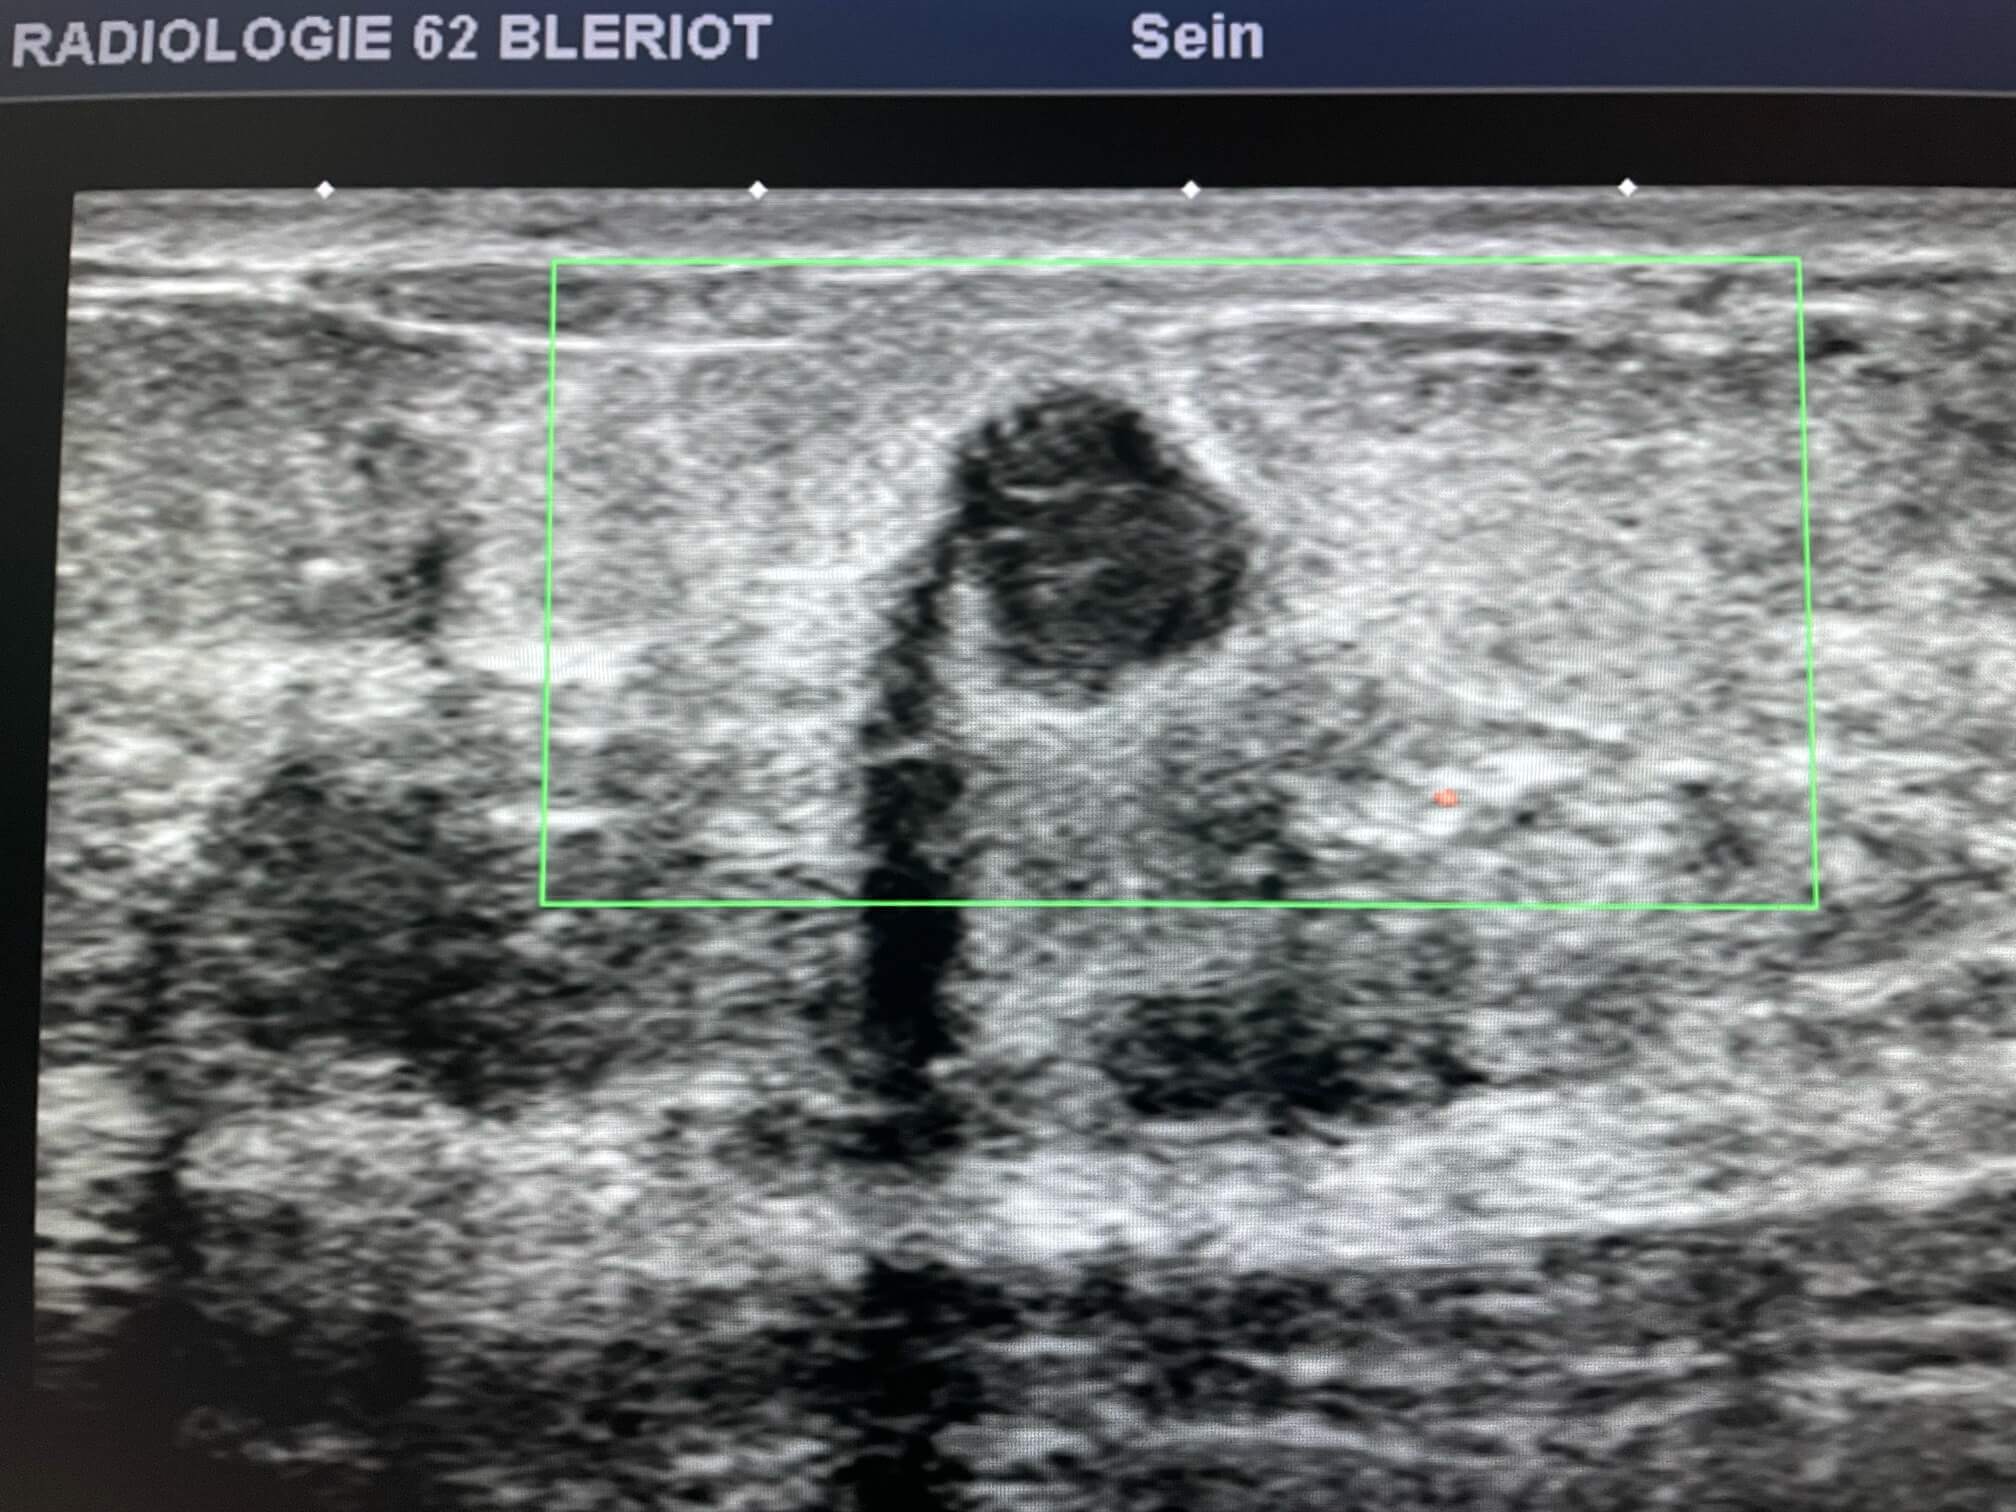

Mammoscreen pointe un surcroît d’opacité d’aspect bilobé supéro externe du sein droit.

L’échographie retrouve une lésion hypoéchogène à contours précis mais discrètement irréguliers.

La biopsie confirme un carcinome infiltrant SBR III RH-, Her2+.